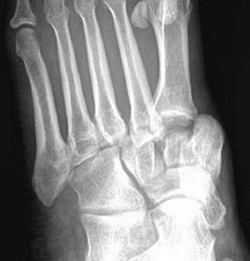

Переломы плюсневых костей

Переломы плюсневых костей по частоте занимают первое место среди всех переломов костей стопы. Обычно возникают при прямом воздействии травмирующей силы (сдавление стопы, падение тяжести или переезд стопы колесом). Могут быть множественными или одиночными. В зависимости от уровня повреждения выделяют переломы головки, шейки и тела плюсневых костей.

Одиночные переломы плюсневых костей очень редко сопровождаются значительным смещение фрагментов, поскольку оставшиеся целыми кости плюсны выполняют функцию естественной шины, удерживая отломки от смещения.

При одиночных переломах плюсневых костей выявляется локальный отек на тыле и подошве, боль при опоре и прощупывании. Множественные переломы плюсневых костей сопровождаются выраженным отеком всей стопы, кровоизлияниями, болью при пальпации. Опора затруднена или невозможна из-за боли. Возможна деформация стопы. Диагноз подтверждается данными рентгенографии в 2-х проекциях, а при переломах основания костей плюсны – в 3-х проекциях.

При переломах костей плюсны без смещения накладывают заднюю гипсовую шину сроком на 3-4 недели. При переломах со смещением проводят закрытое вправление, выполняют открытый остеосинтез или накладывают скелетное вытяжение. Срок фиксации при таких переломах костей стопы удлиняется до 6 недель. Затем пациенту накладывают специальную гипсовую повязку «с каблучком», а в последующем рекомендуют использовать ортопедические вкладки.